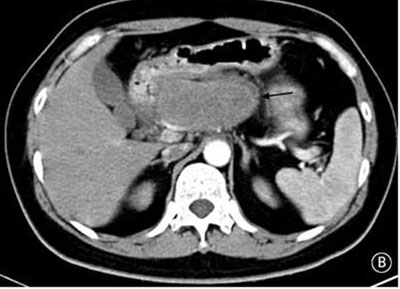

就診時實驗室檢查結(jié)果顯示嚴(yán)重高血糖(血糖水平為982mg/dL[55mmol/L])。腹部CT檢查顯示胰頭部位出現(xiàn)一個9cm大小的腫塊(如圖B箭頭所示)??崭寡逡雀哐撬厮綖?30pg/ml(正常值≤80pg/ml)。